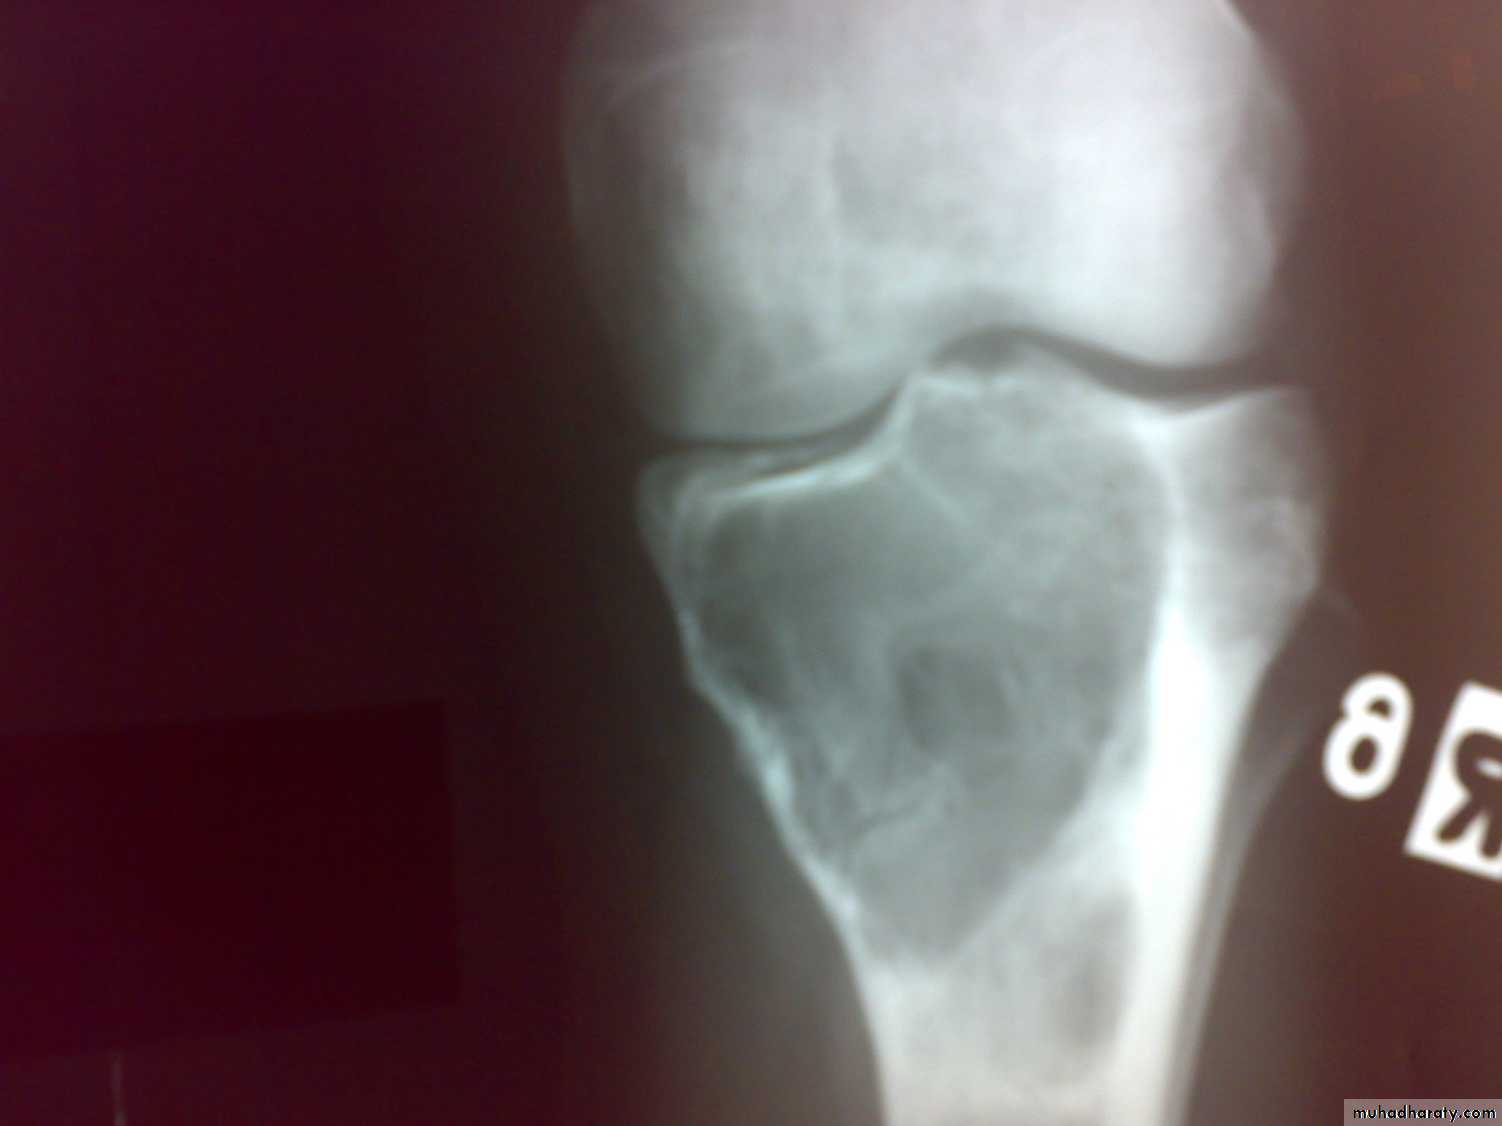

Patient presented by local pain and swelling or pathological fractures. Common site is the distal femur, proximal tibia, distal radius.

X-ray show eccentric osteolytic lesion in the end of long bone ,subchondral, trabeculated (soap bubble appearance). The cortex is thin, expanded or even perforated.